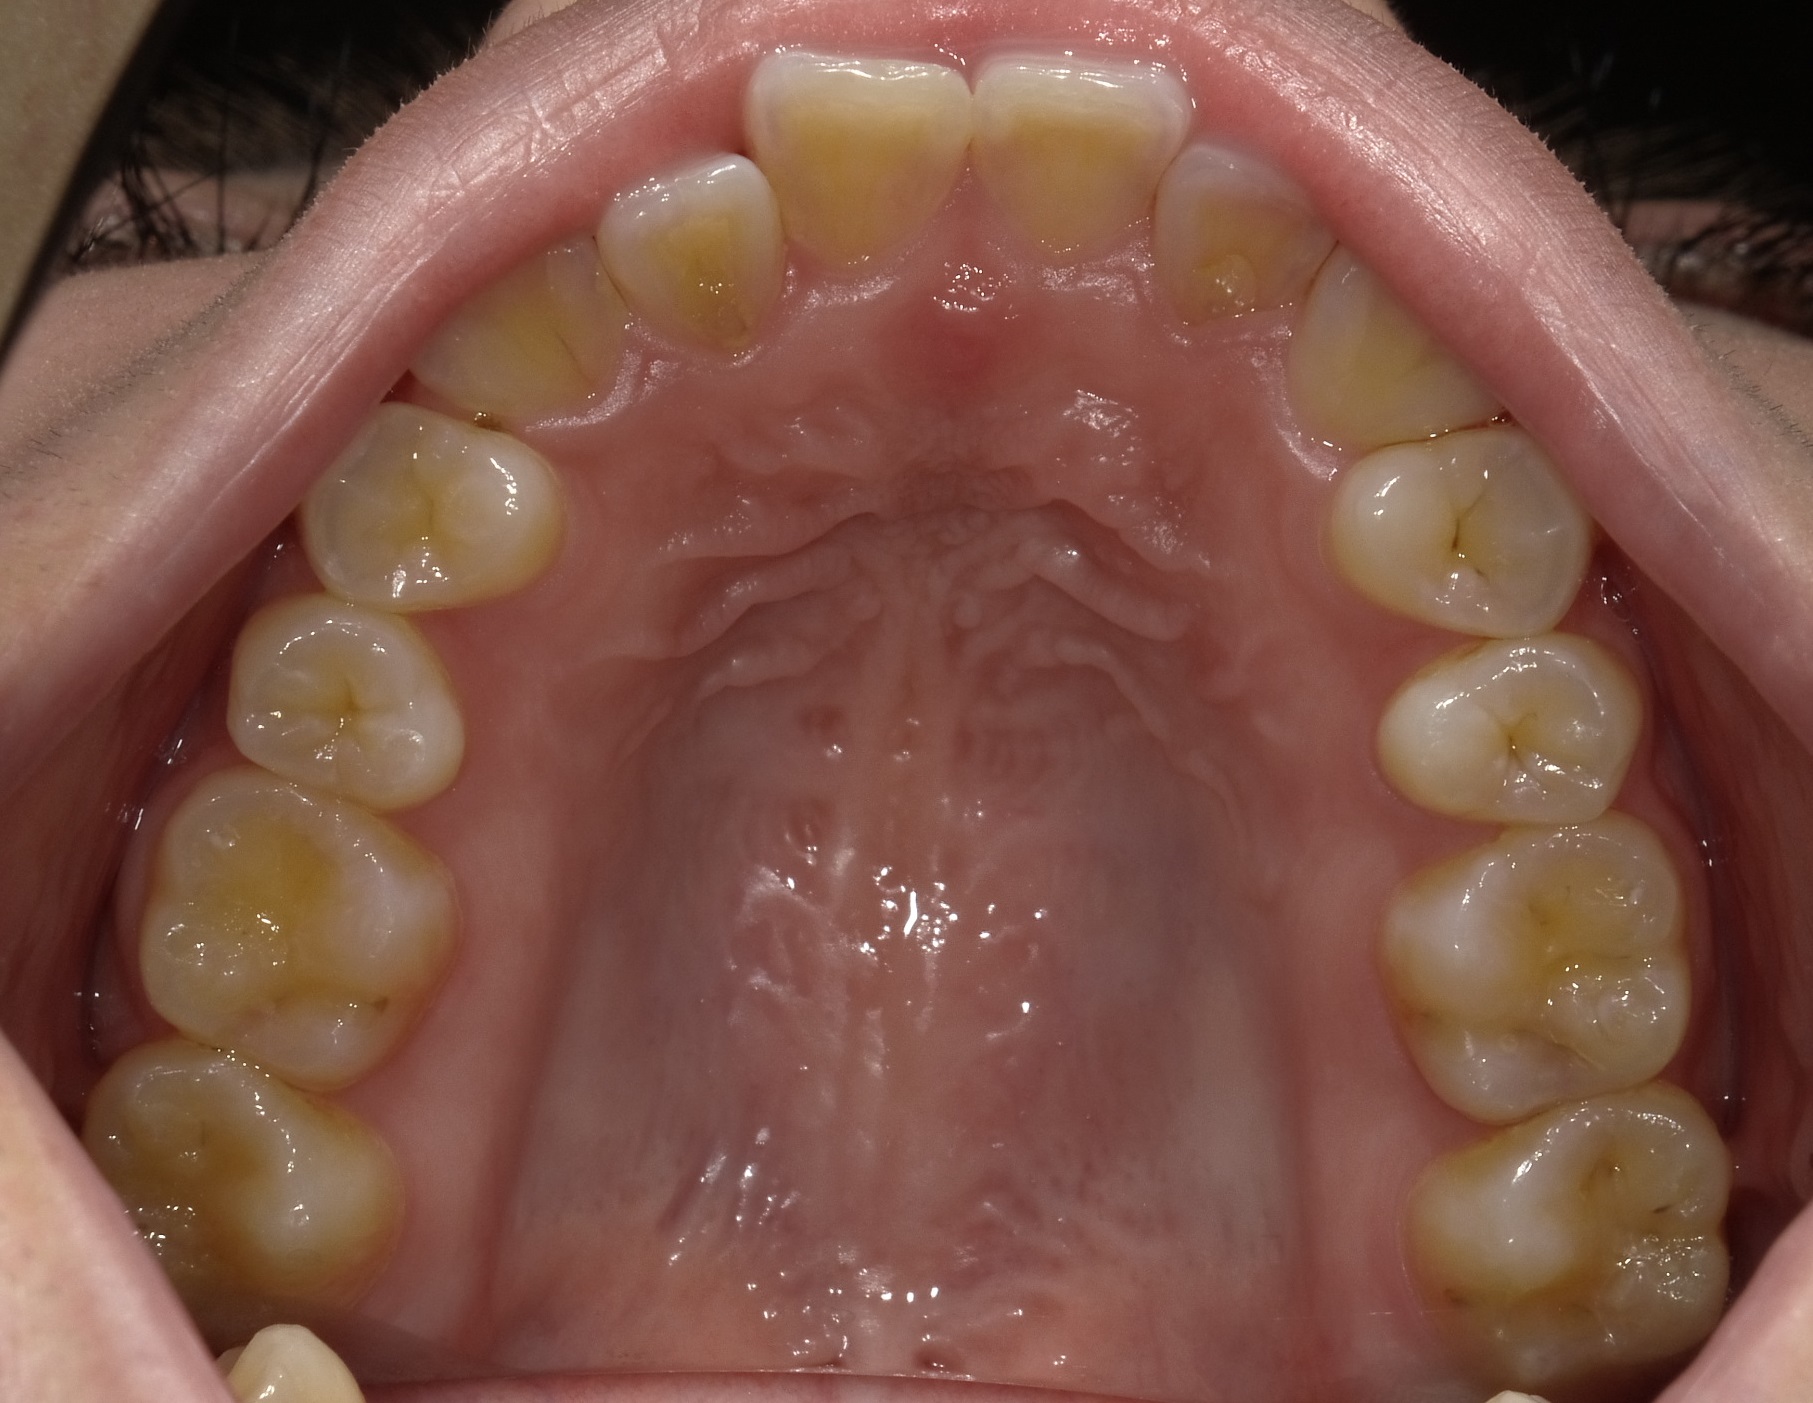

次は上下の歯列の写真です。

これだけ見ると、上は少しの並びの悪さ、下に関してはほとんど問題ないのですが、このままだと上記のとおり噛み合わせたときにお互いぶつかってしまうため、右上前歯の引っ掛かりを取り除き、歯並びおよび噛み合わせ、下顎の受け口感、左右差を治していきます。